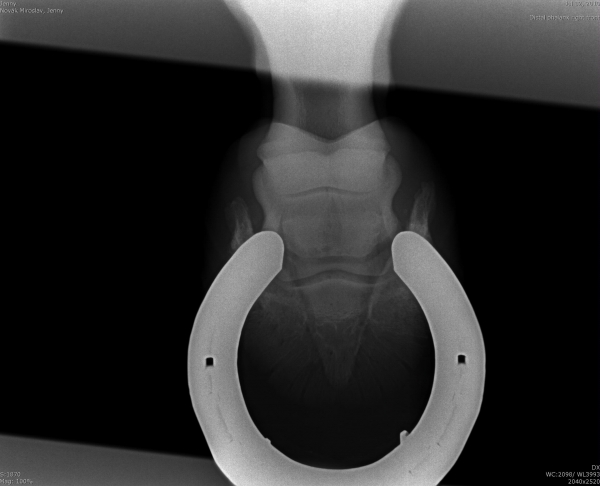

Sam - kladrubský hřebec s laminitídou a výhřezem kopytní škáry, teď krásně chodící a to hlavně díky velké pomoci podkováře, p.Schmidta